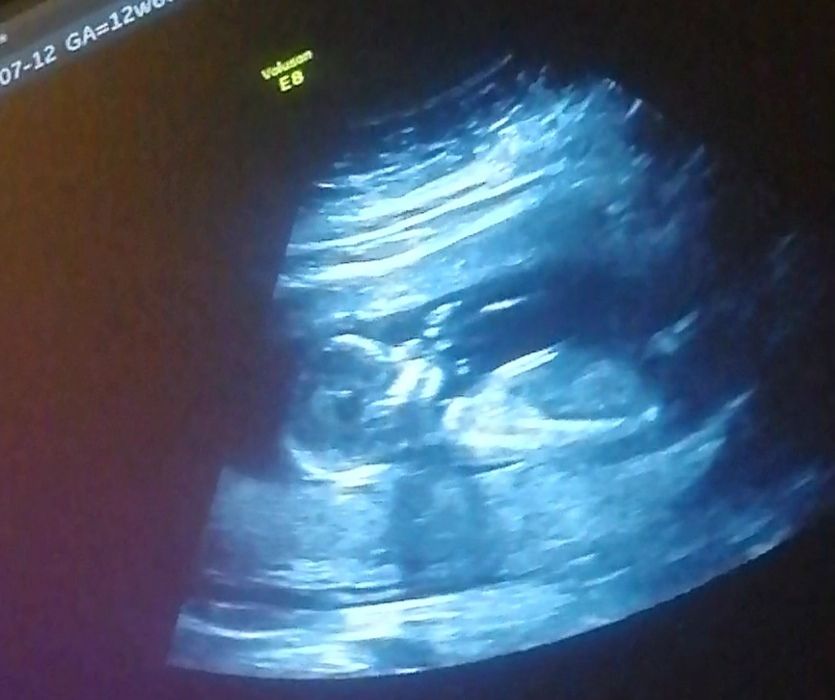

Первый скрининг пройден🥳❤️

Неужели я дождалась и пережила этот волнительный и чудный день🥳

Моя крошечка уже целых 7см,совсем уже человечком стал. Так было интересно наблюдать, как моё чудо сосёт пальчик, а другой ручкой играет с пуповиной🤗 Уже хочется скорее увидеться вживую с малышом, чувства переполняют😍

По узи всё отлично, осталось дождаться кровь, но я уверена, что и там будут хорошие показатели🙏🤞

Решила в недель 15 сходить на узи, узнать пол, на скрининге прятал свою принадлежность, распознать не удалось))